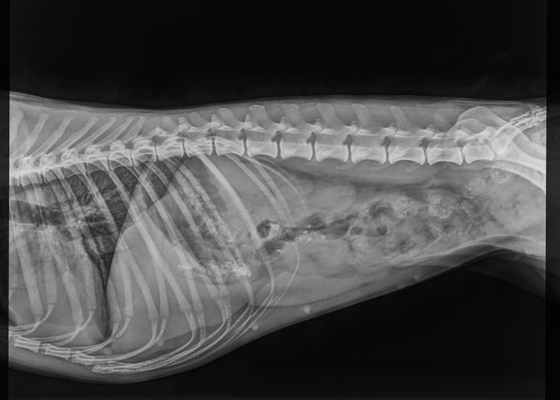

Spine

Spine testing in dogs is a fairly new concept in comparison to the other health tests available.

Spines are scored on three separate points:

Vertebral anomalies (VA)

Lumbosacral transitional vertebra (LTV)

Spondylosis (SP)

Each being scored from 0-4.

For those interested in testing Spines, we recommend the Finnish testing scheme INCOC for the most complete diagnosis.